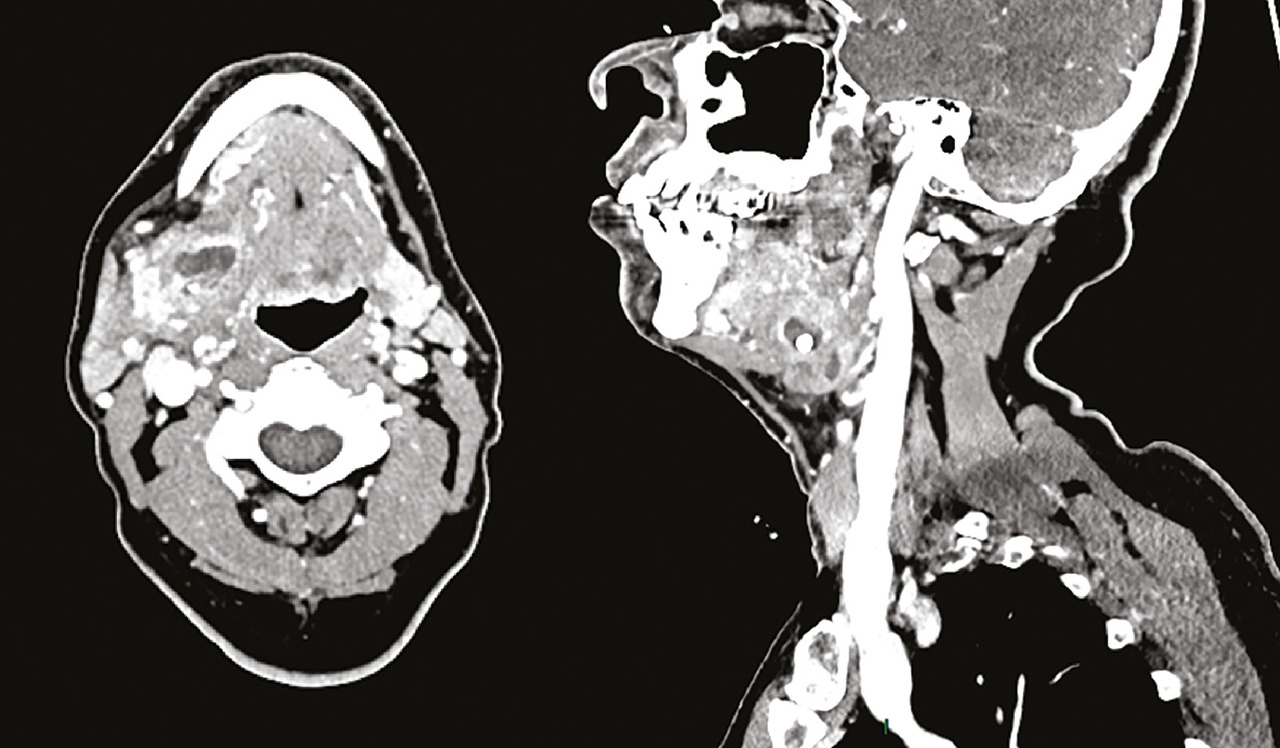

Un examen d’imagerie n’est pas nécessaire en première intention. Cependant, en cas de doute diagnostique, l’échographie est l’examen de première intention : elle montre une glande augmentée de volume, hypoéchogène, avec parfois une dilatation canalaire ou une lithiase visible.6 Elle confirme le diagnostic et recherche des signes de complication comme l’abcès ou la cellulite. Dans ces cas, un scanner avec injection peut orienter vers un traitement chirurgical (Figure ).